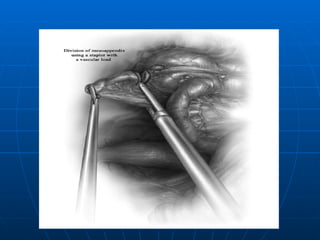

TRATAMIENTO LAPAROSCOPICO Excelente Iluminación y exposición del campo operatorio Disminución de Complicaciones Mayor costo (equipos- anestesia general) Mayor tiempo Operatorio ( 3 Trócares umbilical,suprapúbico (10mm y fosa iliaca izquierda 5mm). En todos los grupos cuando el Apéndice es normal  no se extrae (no así en las convencionales)

TRATAMIENTO LAPAROSCOPICO ExcelenteIluminación y exposición del campo operatorio Disminución de Complicaciones Mayor costo (equipos- anestesia general) Mayor tiempo Operatorio ( 3 Trócares umbilical,suprapúbico (10mm y fosa iliaca izquierda 5mm). En todos los grupos cuando el Apéndice es normal no se extrae (no así en las convencionales)